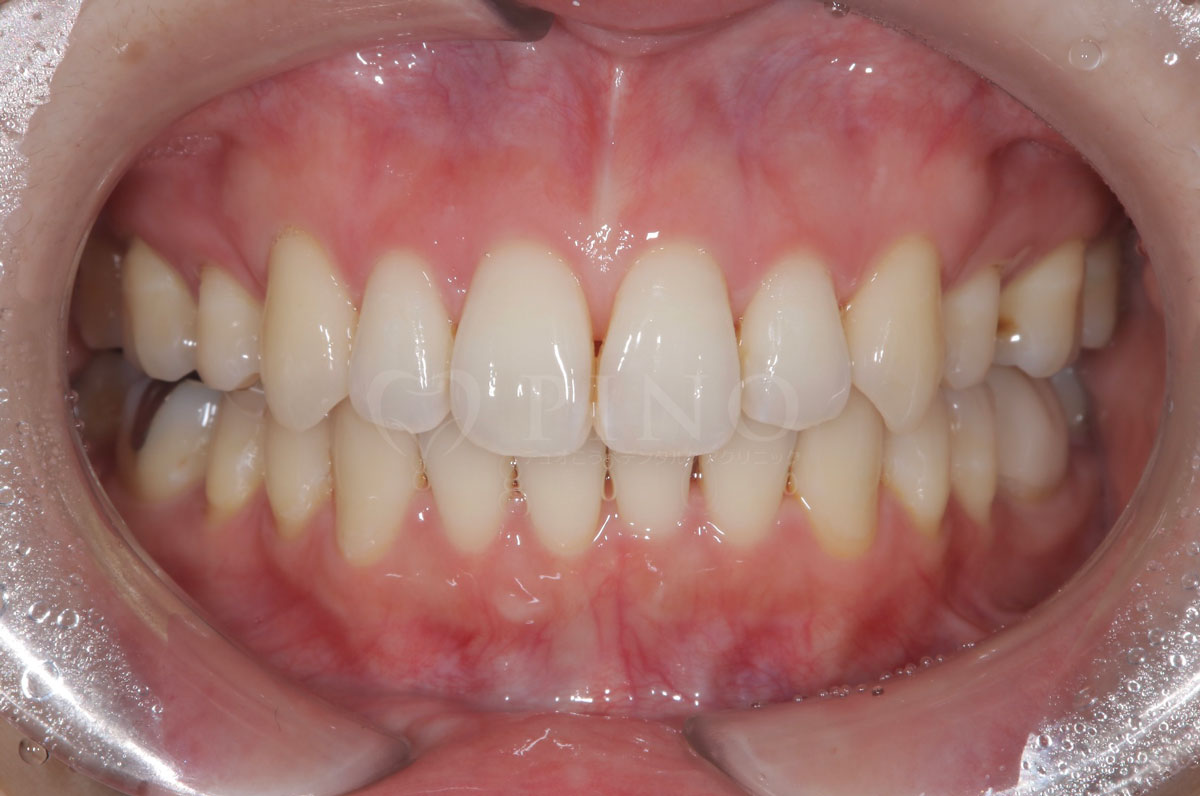

症例2:ワイヤー矯正後の後戻りが気になる(50代女性)

主訴 ワイヤー矯正後に後戻りが気になる 診断名 叢生 治療方法 マウスピース部分矯正 抜歯 なし オルソパルス なし 治療期間 10ヶ月 費用 436,000円+補綴費用360,000円 副作用・注意点 矯正後の後戻りを防ぐためリテーナーの使用が必要となる 備考 1年4ヶ月で補綴も完了した -